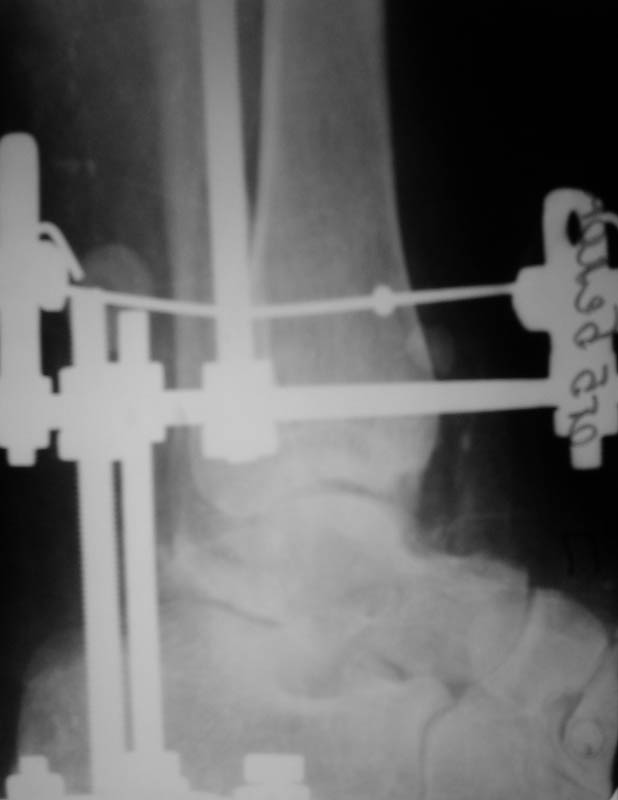

Диагноз: закрытый переломо-вывих таранной кости, двухлодыжечный перелом, подтаранный вывих стопы, асептические некрозы. Перелом был закрытый, но были некрозы из-за давления отломков (см.фото).

Что сделали. Под наркозом попытка закрытой ручной репозиции - безуспешно. Латеральный доступ, открытая репозиция таранной кости. Наложение АВФ (2 кольца, 2 полукольца на пятке и переднем отделе стопы). Устранение подтаранного вывиха стопы. Послеоперационные снимки в приложении.

Рекомендованную медикаментозную терапию получает. Баротерапия. По поводу повторной операции - пока нет особых мнений.

Оценка проведенного лечения?

Фото послеоперационых снимков немного не в фокусе еще к тому же.

Да, сейчас вроде все грубые смещения устранены, но таран какой-то деформированный, а за счет нерезкости снимка не очень понятно, за счет чего. Оценивайте симптом Hawkins через 6-8 недель - если остеопороз блока появится к этому сроку, то он живой...

При переломах тарана аппарат хорош для временной фиксации, а окончательная предпочтительнее в виде минимальной внутренней, например, компрессирующими винтами, введенными через проколы. И сразу после заживления ран аппарат можно снять, и заниматься

движениями, не опасаясь, что фрагменты таранной кости разъедутся. Если отломки тарана фиксировать спицами с упорами в аппарате, чем мы раньше увлекались, то это создает трудности с разработкой.

Какие причины, что Вы не фиксировали перелом. На мой взгляд 2 шурупа позволили Вам начать движения в голеностопном суставе. Кроме того Вы пишите, что у больной двухлодыжечный перелом. Судя по снимкам эти переломы так-же не зафиксированы. По сути дела Вы применили аппарат Илизарова вместо гипса как средство иммобилизации, не использовав возможности метода Илизарова.